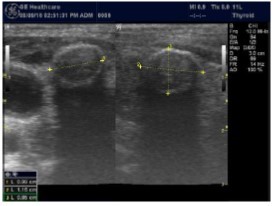

The superficial location of the thyroid gland renders it ideal for ultrasound examination 8. High resolution grey scale images can easily be obtained using high frequency transducer. In the transverse view, normal thyroid gland has the butter fly appearance, with left and right lobes connected with a narrow isthmus, Figure 1A. Both lobes can be imaged separately in the longitudinal plan, Figure 1B